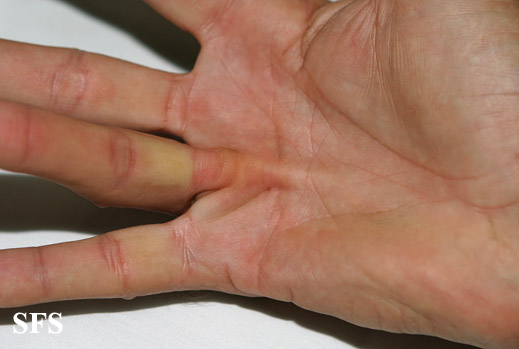

dupuytren contracture